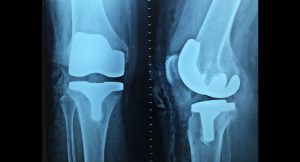

Now the Canary Health Implantable Reporting Processor, known as CHIRP, has arrived. Researchers at Zimmer Biomet immediately noticed that the size, equivalent to a single triple-A battery, and flexibility made the CHIRP a great candidate for sensor technology in knee implants. Embedded in the tibial extension segment of the prosthesis, the sensor power source and transmitter exist on a 1x1.5 millimeter chip.

The sky’s the limit on finding ways to use the processor as a diagnostic tool. Smart-tech screws in implants could help run tests on bones, organs, and even the heart if specifically designed for it. “We’re going to start to be able to get into smaller and smaller and more intricate devices as we go forward,” Dr. Hunter said. Zimmer Biomet will introduce CHIRP sensors in the Persona-IQ, the newest model of its personalized Persona Revision knee implants. Both Zimmer Biomet and Canary Health are working on a reimbursement deal to incentivize physicians to monitor CHIRP data.